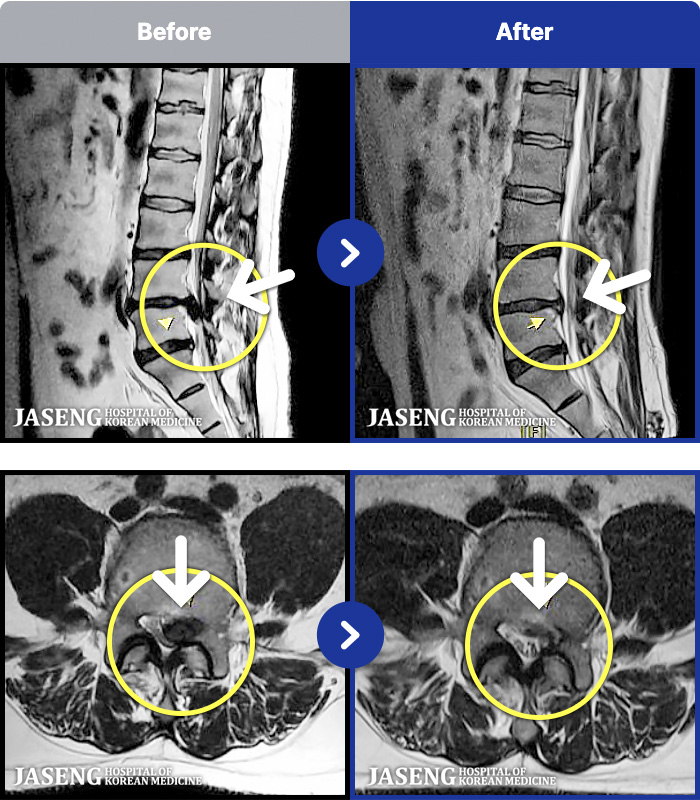

MRI ġ

1,237 MRI ũ ʸ Ȯϼ.